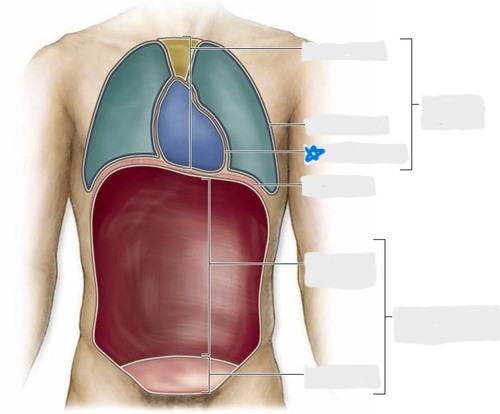

pleural cavity

pericardial cavity

mediastinum

abdominal cavity

pelvic cavity